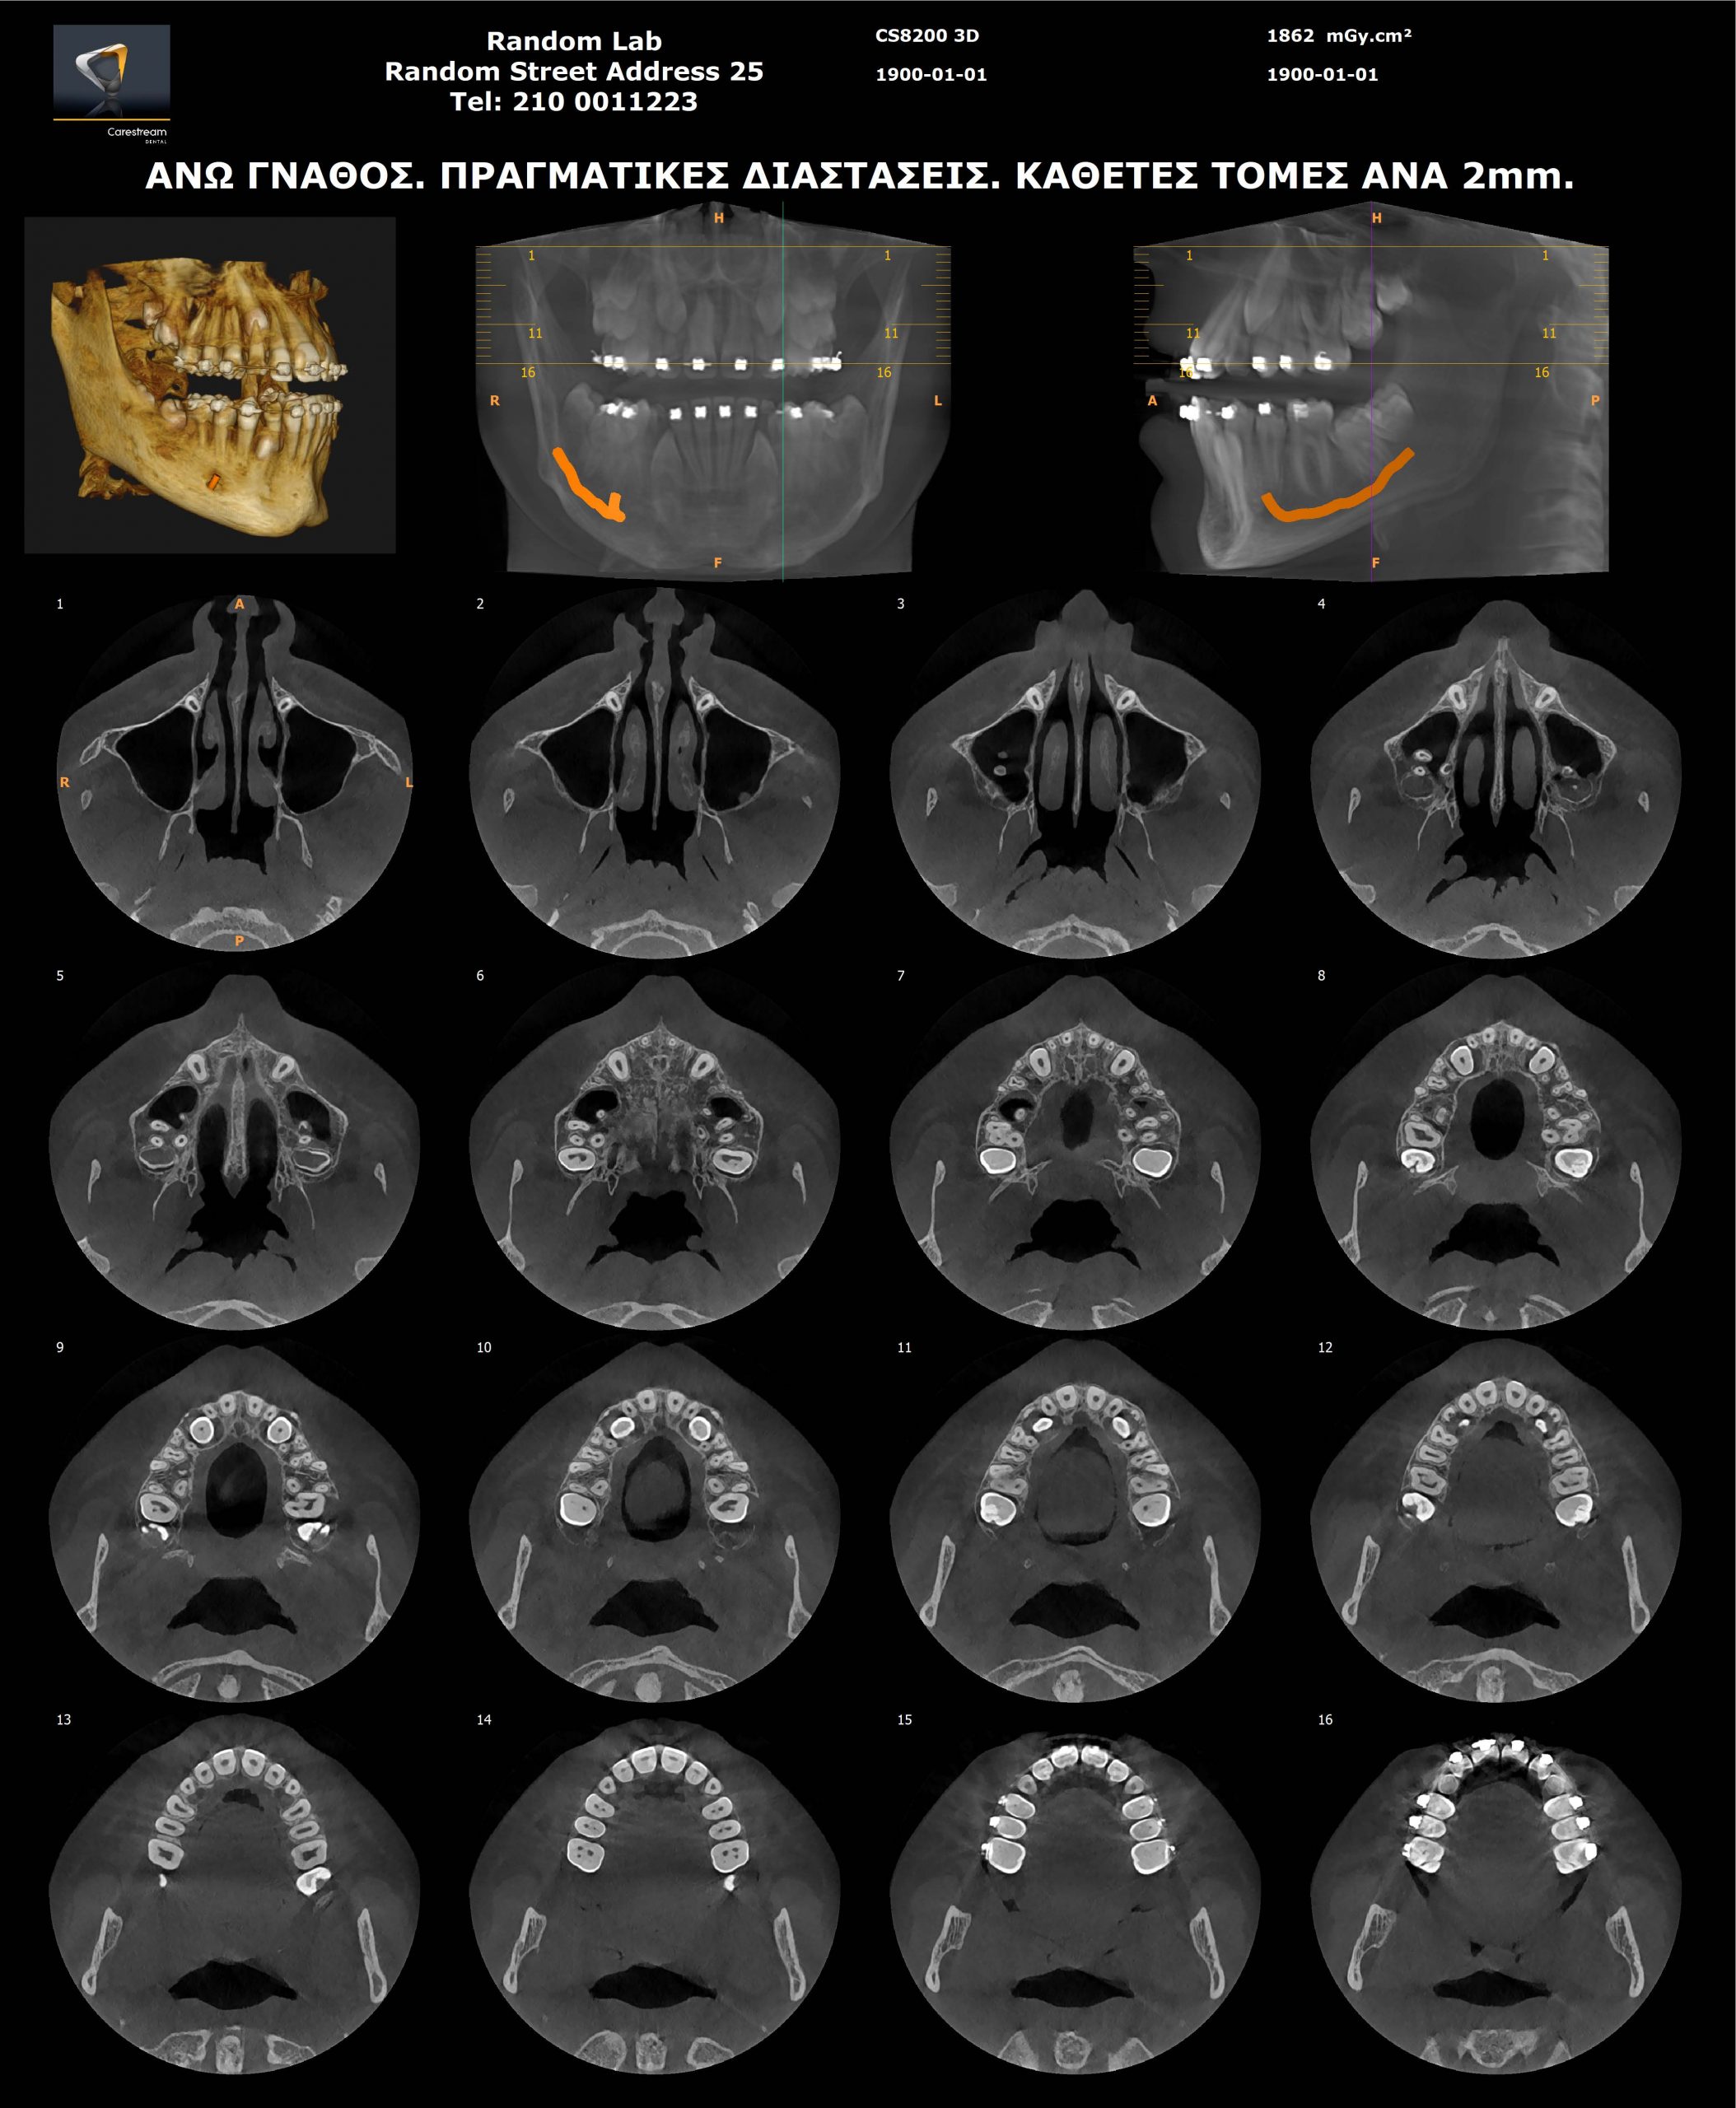

Ογκομετρικός Τομογράφος

- Oγκομετρικό τομογράφο – CBCT (3D) πολλαπλών οπτικών πεδίων, αξεπέραστης ποιότητας εικόνας.